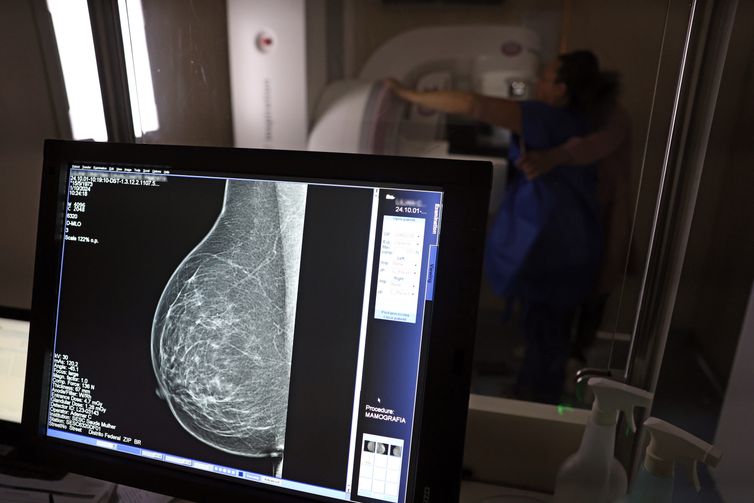

No mês de conscientização sobre o câncer de mama, um relatório destaca a importância de acesso igualitário ao rastreamento e tratamento da doença. Segundo o Atlas da Radiologia no Brasil, do Colégio Brasileiro de Radiologia e Diagnóstico por Imagem (CBR), o acesso aos mamógrafos ainda é um desafio.

O país tem 6.826 equipamentos registrados, sendo 96% em funcionamento. Metade deles está disponível no Sistema Único de Saúde (SUS), responsável por atender 75% da população. Isso equivale a 2,13 mamógrafos por 100 mil habitantes dependentes do SUS.

O Brasil tem uma cobertura muito baixa de mamografias: 24%. O ideal recomendado pela Organização Mundial da Saúde é de 70%. Mesmo em lugares como o estado de São Paulo, que tem a maior concentração de mamógrafos do país, a taxa gira em torno de 26%.

Em setembro, o Ministério da Saúde ampliou as diretrizes de rastreamento, recomendando que mulheres entre 40 e 49 anos realizem mamografias, mesmo sem sintomas. De acordo com o Instituto Nacional do Câncer (Imca), mais de 73 mil mulheres recebem o diagnóstico de câncer de mama anualmente no Brasil.

“O que é efetivo na redução da mortalidade é você descobrir o tumor antes de ter sintoma clínico. Quanto menor o tumor, melhor para a gente descobrir o tratamento e maior a chance de cura. E a gente só consegue fazer isso com exames de imagem", diz Ivie.

Ela explica que no caso de diagnóstico de um câncer de mama com menos de 1 cm, a chance de cura é de 95% em cinco anos, independentemente se ele é do tipo mais agressivo. "E esses tumores só vão ser detectados na mamografia. Essas pessoas que têm que ir fazer mamografia são mulheres saudáveis. Não são mulheres doentes”, acrescenta.